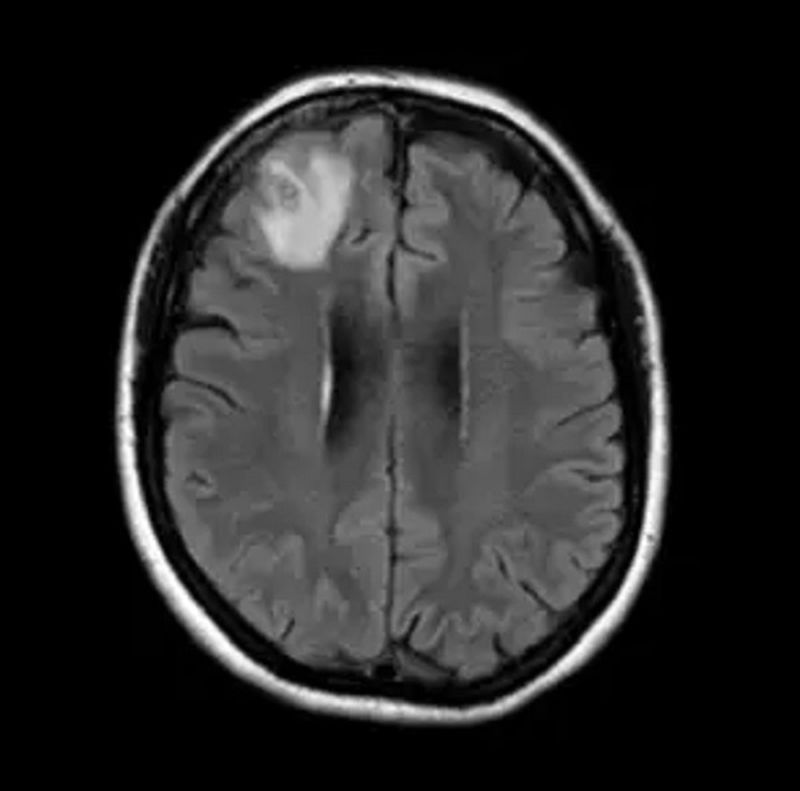

În cursul anului 2022, femeia prezenta și semne de depresie și uitare, așa că medicii au realizat o scanare RMN a creierului ei, care a scos la iveală diverse anomalii.

Imaginea de la RMN i-a determinat pe medici să recomande o intervenție chirurgicală, potrivit The Guardian.